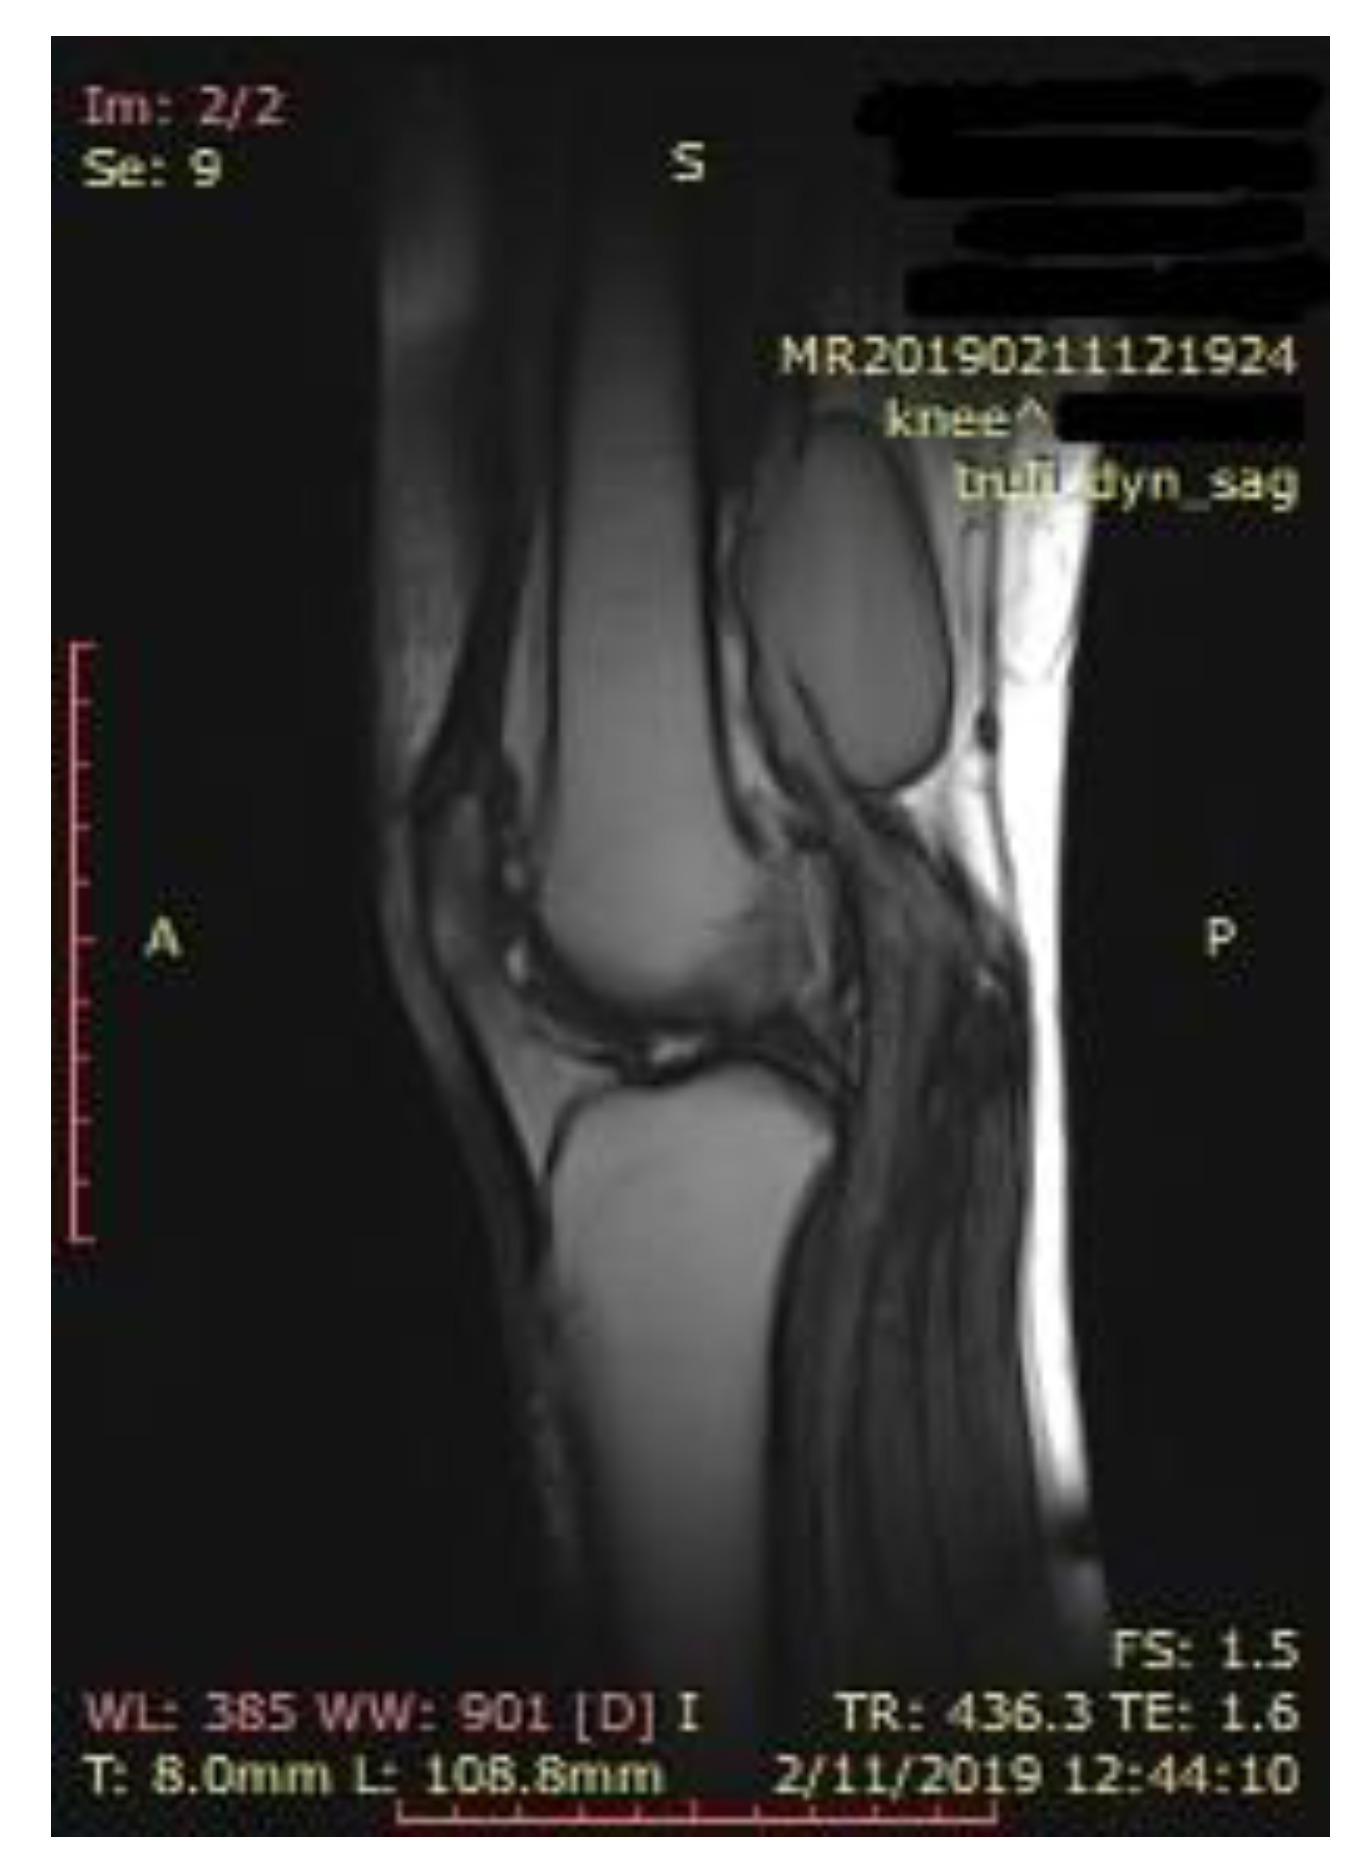

Knee MRI was performed to better describe the extension and anatomy of the aneurysm. It described an aneurysmal dilatation of the distal popliteal vein measuring 64 × 19 × 31 mm, with turbulent blood flow which exerted a mass effect on the adjacent muscle groups (Figure 2).

Figure 2.

Magnetic resonance (MRI) of the knee, longitudinal axis view, showing the anatomy and location of the popliteal vein aneurysm.